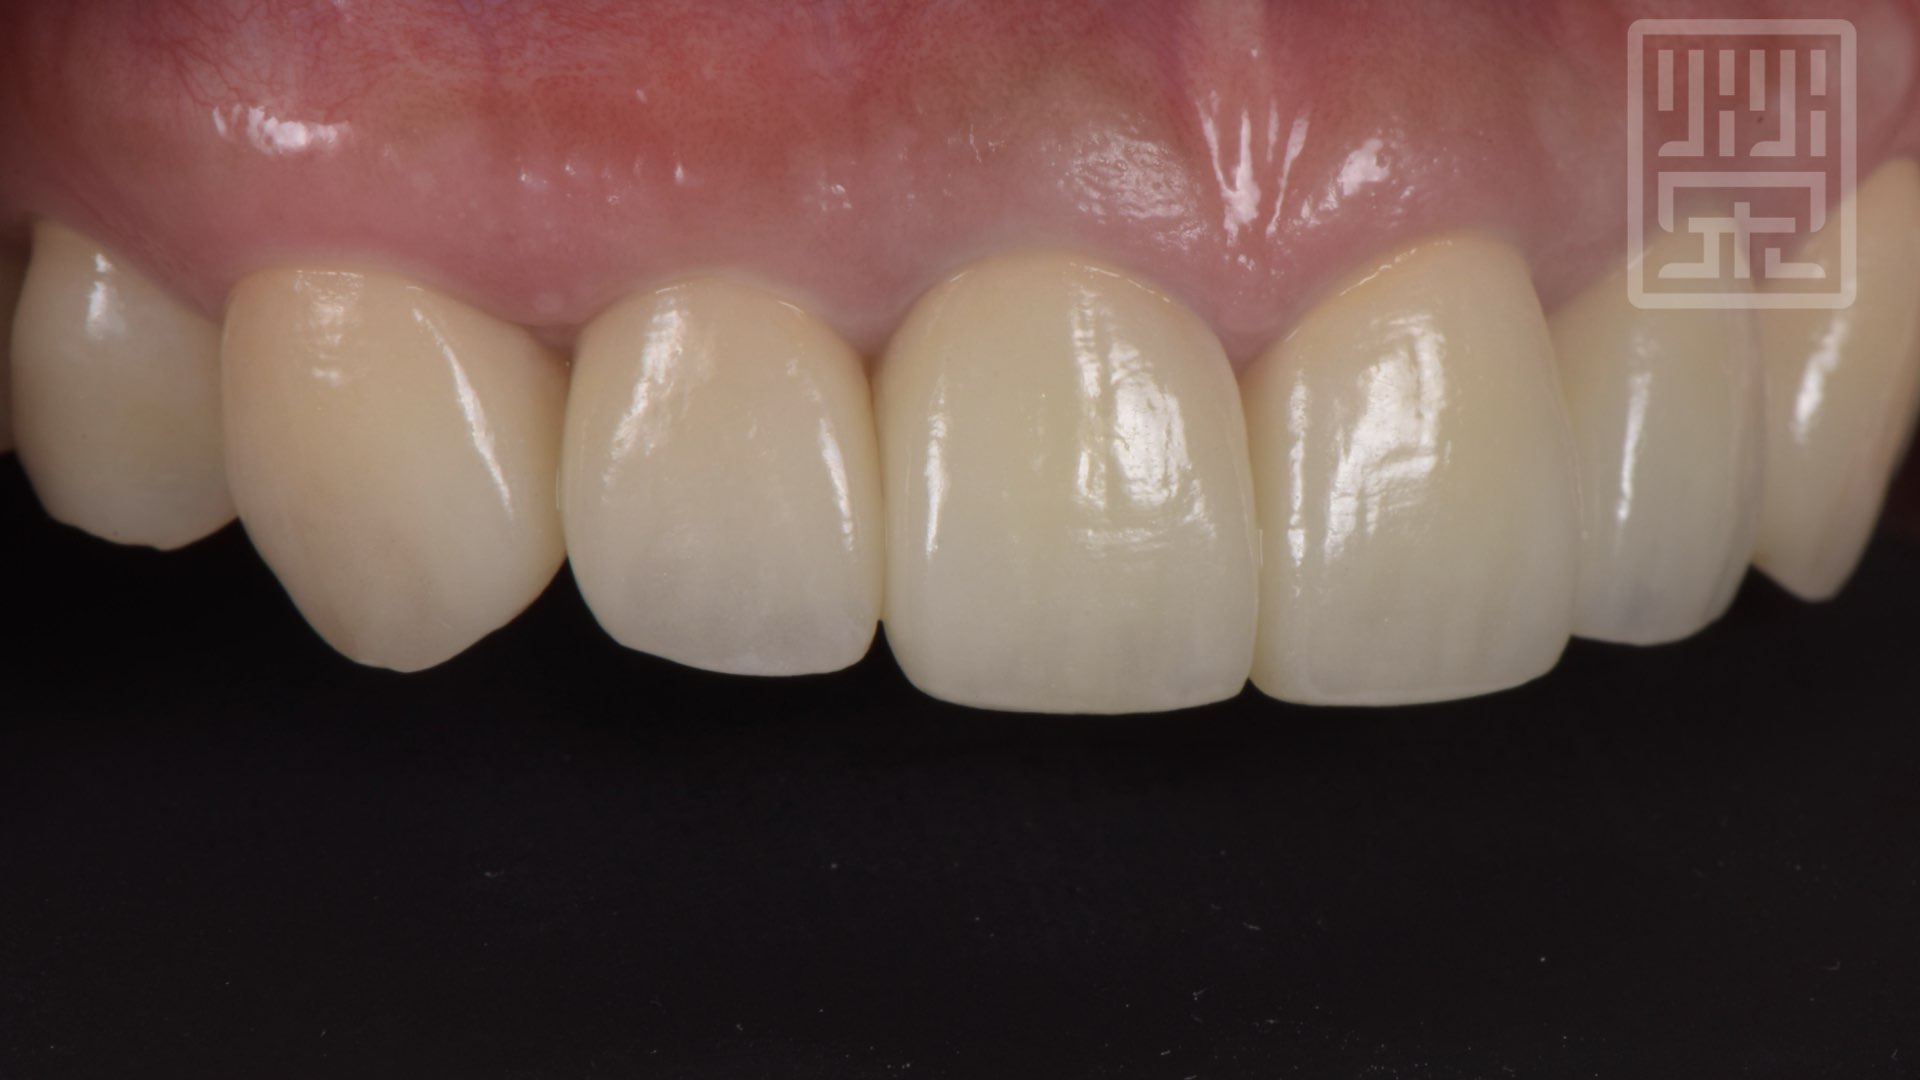

榮醫師建議他兩側上顎犬齒也一起更換全瓷冠,保護牙齒,重新建立保護性咬合。

保護性咬合

保護性咬合痕跡